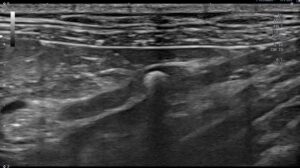

検査の結果、左の尿管結石と閉塞が見られました。

術後のエコーで腎臓の腎盂拡張は改善されています。